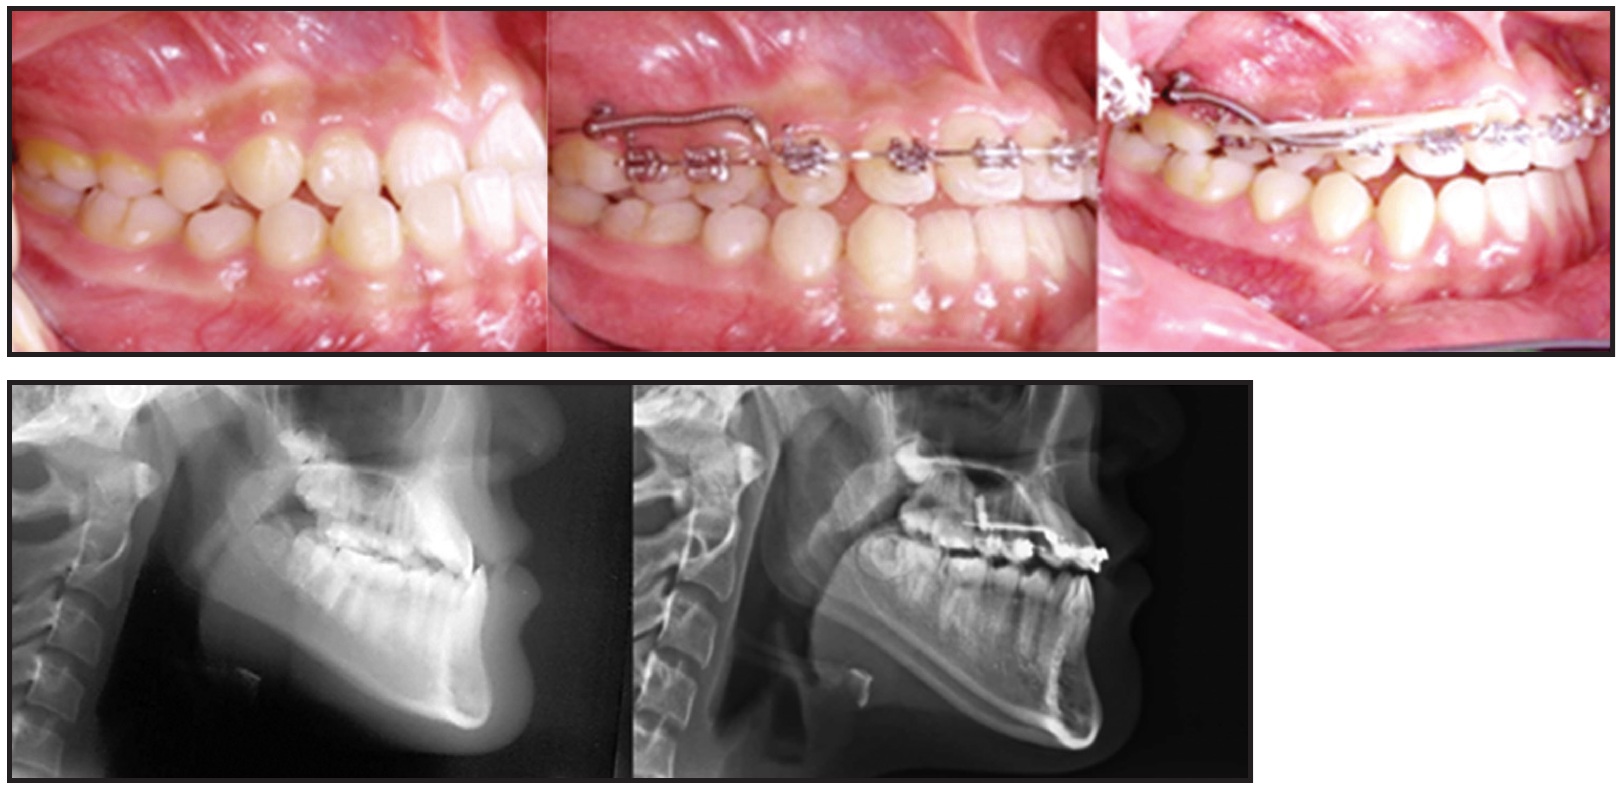

Because of the severe external resorption of the deciduous lower central incisors, we prescribed provisional implant restorations using 1.6mm × 8mm MC-implants.2,11 Instead of a flap operation, considering the loss of anterior alveolar bone, we planned for immediate insertion of the MC-implants following extraction of the deciduous incisors. After infiltration of anesthesia, each deciduous incisor was extracted with forceps, and an MC-implant was inserted in the extraction socket at an angle following the long axis of the extracted tooth (Fig. 6).

Fig. 6 After 26 months of treatment, 1.6mm × 8mm MC-implants inserted as provisional dental implants. A. Resorbed and shortened root observed after extraction of deciduous lower right central incisor. B. MC-implants placed in extraction sockets, following original long axes of teeth. C. MC-implants in position.

The stability of the MC-implants was confirmed radiographically after insertion (Fig. 7).

Fig. 7 MC-implants at center of alveolar bone housing, parallel to adjacent lateral incisors.